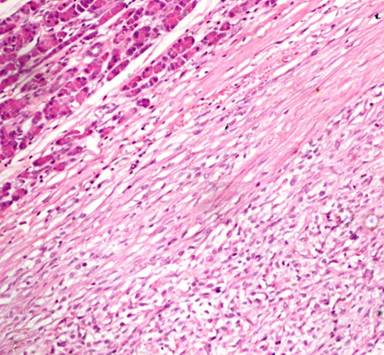

A 11-year-old male presented with complaints of painless hard swelling involving left lumber, umbilical and left hypochondrium of abdomen. According to his mother he was apparently asymptomatic 20 days back when he incidentally noticed firm to hard swelling in left upper abdomen. No history of fever, vomiting, jaundice, weight loss and hematemesis and bleeding per rectum was seen. No family history of a genetic disease was seen. Clinical examination was normal. Body fluid amylase was 4,800 U/L (reference range: 4-234 U/L) and liver function tests were normal. Computed tomography (CT) revealed a large mass measuring 10.0x8.8x7.5 cm in the pancreatic tail, mainly solid but small cystic component (Figure 1). The pancreatic tail mass was well-delimited but not encapsulated. There was no evidence of local invasion or metastasis. The surrounding vessels (celiac trunk, superior mesenteric artery, and splenic and portal veins) were not invaded. The surrounding pancreas was normal. The clinical diagnosis of adenocarcinoma of the pancreas was suspected. Resection of pancreatic tail mass and distal pancreatectomy with splenectomy was performed. Operative findings showed a mass with cyst involving pancreatic tail, adherent to splenic vein and artery, free from stomach and left kidney. The macroscopic examination revealed compressed pancreas measuring 4.0x1.0x0.5 cm, spleen measuring 8.5x6.0x3.5 cm with mesentery measuring 3.0x3.0x0.5 cm. and a well circumscribed, non-encapsulated, dense, mesenchymal tumor measuring 10.0x8.8x7.5 cm with a cystic area measuring 1.5 cm in diameter (Figure 2). Outer surface of the tumor was grey white and lobulated. No lymph node was seen. Histological examination showed a circumscribed tumor arranged in intersecting fascicles infiltrated the surrounding pancreatic parenchyma (Figure 3).Tumor cells are mildly anisomorphal with spindle shaped cells having elongated nuclei with blunt ends and bipolar cytoplasm. Mitosis is infrequent (less than 1-2 per 10 high power fields). Necrosis was not seen. Spindle shaped cells have a regular nucleus and were separated by large amounts of collagen fibers in edematous tissue with some inflammatory cells (Figure 4). The cystic component was seen within the tumor. Spleen showed congestion and focal fibrosis. Immunohistochemical analysis revealed that the tumor cells were strongly positive for beta-catenin (Figure 5), vimentin (Figure 6) and negative for cytokeratin (CK), CD34 (Figure 7), S100, CD68, CD117, smooth muscle actin (SMA) (Figure 8), muscle specific actin, desmin, CD99, Bcl2, anaplastic lymphoma kinase 1 (ALK-1) and human melanoma vlack 45. Proliferation marker Ki67 stained about 2% of the tumor cells. The immunohistochemistry and histopathological features were consistent with a confirmed diagnosis of desmoid tumor. A short term follow-up showed rapid disappearance of the symptoms which had revealed the desmoid tumor. Because of complete resection and the sporadic origin of the desmoid tumors, no corresponding treatment was given. After 10 months of follow-up, the patient is well and normal on clinical examination.

Figure 3. Section showed tumor composed of sheets of spindle shaped cells with bland nuclear morphology, fine chromatin, inconspicuous nucleoli and mild cytoplasm along with adjacent normal pancreas (H&E x40 magnification). |